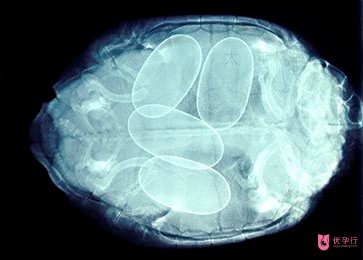

筆者建議:選擇第三代俄羅斯試管嬰兒PGS/PGD基因篩查診斷技術(shù)。第三代試管嬰兒技術(shù)可準(zhǔn)確篩查出染色體異常夫妻的問(wèn)題胚胎,通過(guò)PGS/PGD技術(shù),可將胚胎中全部染色體與多達(dá)125種遺傳性疾病進(jìn)行準(zhǔn)確檢查;

如此,在胚胎植入前便可知道哪些是存在致病基因的不良胚胎,哪些是可植入的優(yōu)質(zhì)健康胚胎。